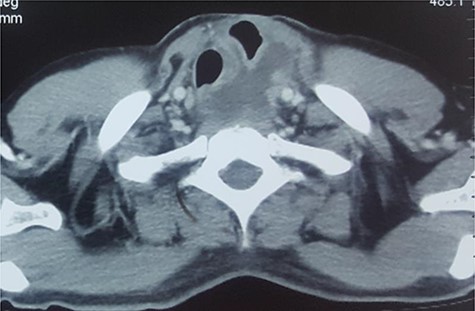

After unremarkable 18 months of the second surgery, he presented with a few days’ history of fever, dysphagia and a painful swelling in the left neck. There was an erythematous, hot cystic swelling measuring 6 cm × 5 cm in the neck underlying the earlier incision. Ultrasound of the neck revealed a loculated collection with some debris, without significant cervical lymphadenopathy. A contrast esophagram was performed which showed an intact esophagogastric continuity without obstruction, stricture, dilatation, leakage or delayed gastric emptying. A CECT scan revealed a distended blind-ended native esophagus filled with high-density fluid extending from neck to the diaphragmatic hiatus (Figs 1 and 2).

CECT of neck. Note the upper end of the pyocele displacing the trachea and the gastric conduit anteriorly and towards the right.